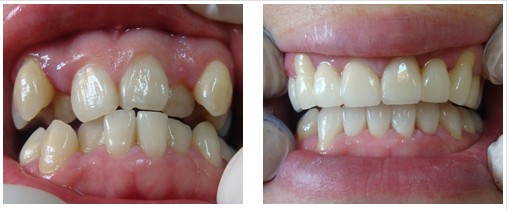

牙齿矫正没有年龄的限制。当然,青少年新陈代谢快,适应能力强,牙齿矫正需要的时间也相对较短。但这绝不是说牙齿矫正仅限于未成年人。成年患者只要牙齿自身的牙周状况允许,是完全可以接受牙齿矫正的。

现代牙齿矫正高度发达,牙箍的种类也越来越多,已经完全可以做到隐形矫正。而且随着的进步,隐形矫正的适应症也越来越广,以往一些被视为禁忌的疑难病例也可以得到很好的隐形矫正,对工作生活几乎没有什么影响。

广州越秀圣贝口腔门诊部口腔的美颜正畸系统采用计算机辅助三维诊断、个性化设计以及数字化成型,智能控制每颗牙齿的移动,预测牙齿矫正后的位置,在矫治前用计算机模拟临床牙齿移动方式,让患者更清楚的感受矫正后的效果和所需要的时间,实现矫正模拟过程及结果的三维可视化。它根据面部特点进行个性化设计,通过改变牙齿排列关系、上下颌的咬合关系,以及牙列及牙槽骨的排列关系,解决颌骨、颅面的不协调,重塑美好颜面,达到面部整体的和谐美。

广州越秀圣贝口腔门诊部口腔的美颜正畸系统采用特殊的矫正装置,可自行摘戴,不影响社交、进食、运动等,大限度地减少了复诊次数,并缩短了矫正时间,节约了顾客的宝贵时间。由于没有传统意义上的托槽、钢丝等矫正装置,矫正过程不再痛苦,佩戴时光滑舒适,无异物感和粘膜刺激,矫正过程舒适轻松,对牙周组织的刺激及不适感低。口腔卫生容易维护,不必担心牙龈炎、牙齿脱矿、变色等问题。